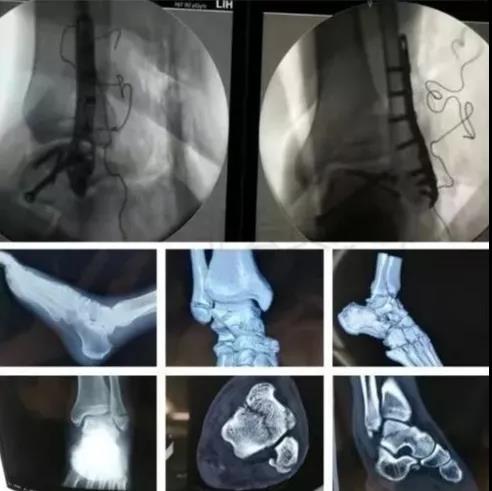

7)胫骨远端(pilon,踝部)

- pilon骨折,高能损伤,6-8h肿胀未形成,可以急诊做,手术时间<3小时。

- 10-14天,分步延期手术策略。

- 踝部骨折手术时机同样取决于皮肤条件。